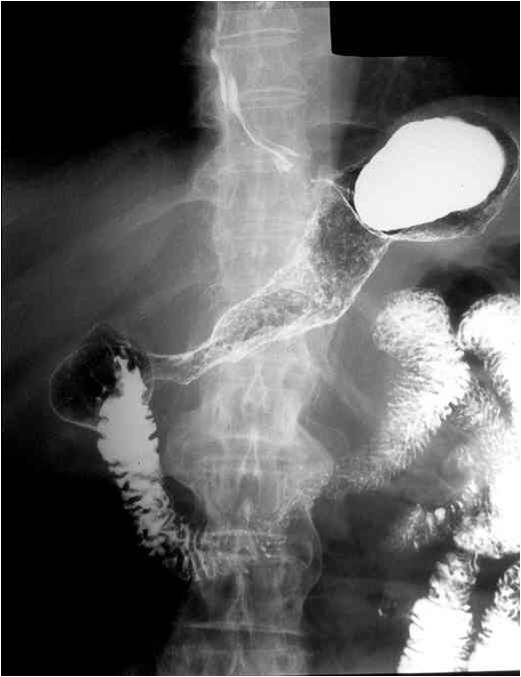

Image

Fig.20.: Follow-through examination

On the abdominal radiograph distension of the small bowel loops and air-fluid levels can be identified. It is important to describe forwarding of the contrast media by time or if mechanical obstruction is seen. Morphology of the intestinal loops could not be assessed with this method. This study is specifically conducted to examine the transit function only.

Fig.21.: Radiograph of selective enterocylsis